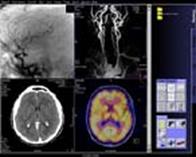

Все томографы фирмы SIEMENS объединяет единый интерфейс пользователя – syngo. Помимо стандартных закладок Examination, Viewing, Filming имеется закладка 3D с возможностями осуществлений MPR – (в реальном времени) и MIP-реконструкций.

Программно и технически (в комплект поставки вошел автоматический инъектор Medrad CT Tripak CTP-200-FLS) реализованы возможности КТ-ангиографии. Имеется опциональная программа Pulmo CT для исследования легочной эмфиземы.

Рисунок 9 – Интерфейс пользователя